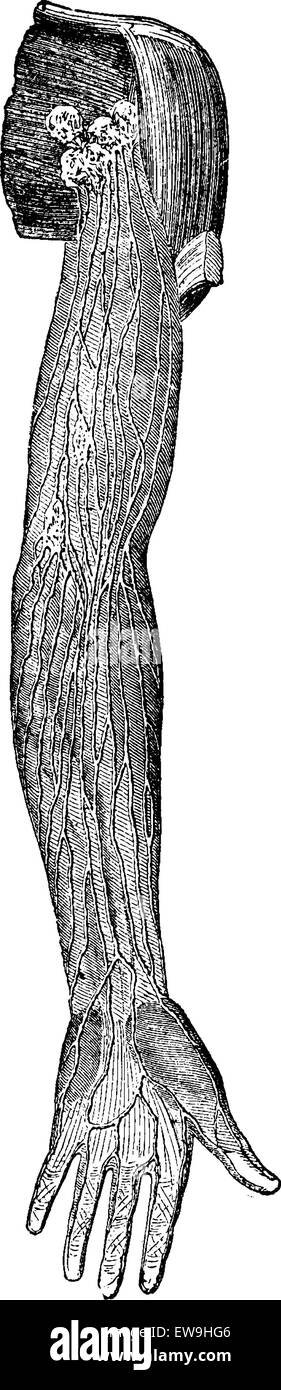

RFEW9HG6–Oberflächlichen Lymphgefäße der oberen Extremität, graviert Vintage Illustration. Üblichen Medizin Wörterbuch - Paul Labarthe - 1885

RFEW91T9–Oberflächlichen Lymphgefäße der oberen Extremität, graviert Vintage Illustration. Üblichen Medizin Wörterbuch - Paul Labarthe - 1885